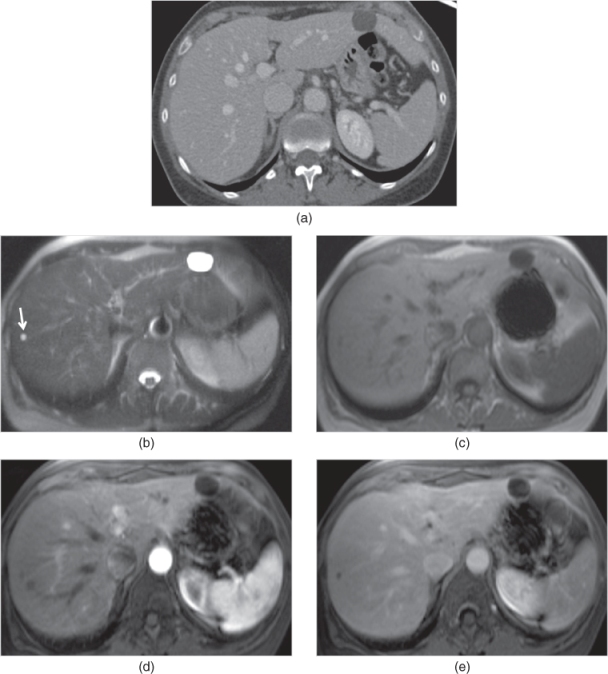

From radiologykey.com

Cystic diseases of the liver Radiology Key Autoimmune Hepatitis And Liver Cysts Autoimmune hepatitis is a chronic, inflammatory disease of the liver that is characterized by circulating autoantibodies and. Autoimmune hepatitis is a disease in which the body’s own immune system attacks the liver and causes it to become inflamed. Nearly all liver cysts are. Health library / diseases & conditions / liver cysts. Autoimmune hepatitis is an inflammatory disease of the. Autoimmune Hepatitis And Liver Cysts.

From www.xiahepublishing.com

Differentiating Cystic Liver Lesions A Review of Imaging Modalities Autoimmune Hepatitis And Liver Cysts Health library / diseases & conditions / liver cysts. Autoimmune hepatitis is a liver disease that happens when the body's immune system attacks the liver. Nearly all liver cysts are. Autoimmune hepatitis is an inflammatory disease of the liver of unknown cause that may progress to liver cirrhosis and end stage liver failure if diagnosis is overlooked and treatment delayed.. Autoimmune Hepatitis And Liver Cysts.